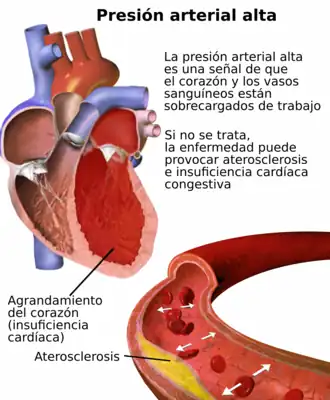

La hipertensión arterial (HTA) es una enfermedad crónica caracterizada por un incremento continuo de las cifras de la presión sanguínea por encima de los límites sobre los cuales aumenta el riesgo cardiovascular. De acuerdo con numerosos estudios internacionales, la morbilidad y mortalidad de causa cardiovascular tiene una relación directa con el aumento de las cifras de presión sistólica sostenida por encima de 139 mmHg o una presión diastólica sostenida mayor de 89 mmHg tanto para las complicaciones de la enfermedad coronaria como para los accidentes vasculares cerebrales, la insuficiencia cardiaca, la enfermedad vascular periférica y la insuficiencia renal.[9][10][11]

La hipertensión es una enfermedad asintomática y fácil de detectar; sin embargo, cursa con complicaciones graves y letales si no se trata a tiempo. La hipertensión crónica es el factor de riesgo modificable más importante para desarrollar enfermedades cardiovasculares, así como para la enfermedad cerebrovascular y renal.

La hipertensión arterial persistente puede causar un accidente cerebrovascular trombótico o embólico, infartos lacunares o un accidente cerebrovascular hemorrágico con hematoma intracerebral, entre otros. Tanto la presión sistólica y diastólica elevadas son perjudiciales; una presión diastólica de más de 100 mmHg y una presión sistólica de más de 160 mmHg han dado lugar a una incidencia significativa de enfermedades cerebrovasculares. Otras manifestaciones de la hipertensión incluyen la encefalopatía hipertensiva, lesiones microvasculares cerebral y la demencia de origen vascular como consecuencia de múltiples infartos del sistema nervioso central.

- Ateroesclerosis progresiva de grandes vasos, en especial de vasos cerebrales, aorta, coronarias y arterias de los miembros inferiores, generando hipoperfusión crónica subclínica o sintomática.

Corazón

- Hipertrofia ventricular izquierda: en inicio hay engrosamiento parietal sin incremento de la masa ventricular total (remodelado concéntrico); luego se desarrolla franca hipertrofia concéntrica, que podría llegar a fase dilatada (hipertrofia excéntrica).

- Insuficiencia cardíaca congestiva (ICC) global; como consecuencia de la falla ventricular izquierda hay además compromiso secundario del hemicardio derecho, con dilatación de cámaras e hipertensión arterial pulmonar secundaria.